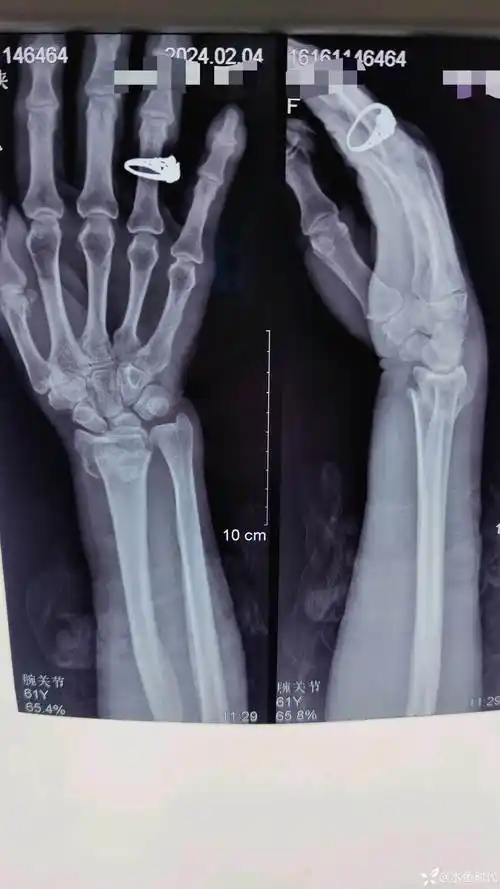

各位老师看看这个colles骨折复位可以不